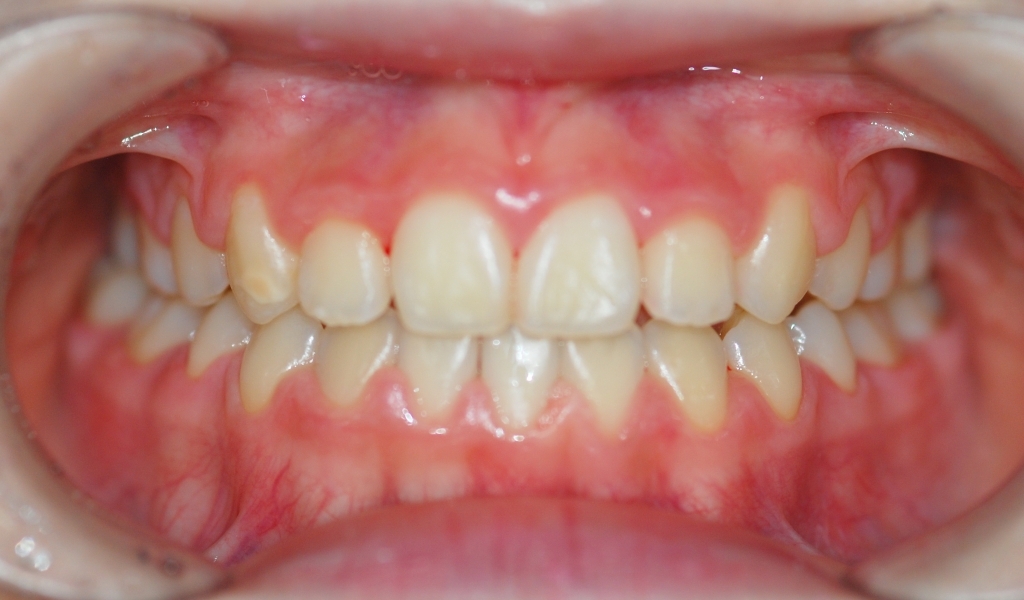

서울보스톤치과에서 치료 받으신 분들의 전후사진입니다.